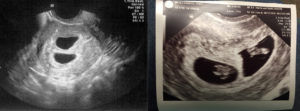

- Ультразвуковое исследование — самый достоверный способ увидеть и определить, какая у женщины беременность, более точный срок беременности, размеры плодов и все патологии, существующие у двоих эмбрионов (если таковые имеются). А также при помощи данного метода возможно определить однояйцевая или разнояйцевая беременность наблюдается у женщины.

Двойню на УЗИ можно увидеть и определить уже на 4-5 неделе беременности. Как правило, однояйцевые близнецы определяются позже, чем разнояйцевые (не раньше 12 недели).

Самый ранний срок, когда можно выявить, произошло ли зачатие, — 5 недель. В это время врач уже способен разглядеть эмбрионы в матке и определить их количество. На этом сроке начинает формироваться детское сердце, и уже с 8-й недели прослушивается ритм двух или более сердечек. Это также сигнализирует о многоплодной беременности.

Поскольку первое плановое УЗИ делается в 10-12 недель, отправить пациентку на ультразвук в 5-6 недель имеет право только лечащий врач. Это может произойти, если доктор заподозрит двойню при обычном осмотре. Основной внешний признак – это слишком большой размер матки, который не соответствует реальному сроку.

Считается, что точно увидеть несколько эмбрионов, можно только при помощи УЗИ. На каком сроке определяют многоплодную беременность? Специалист может увидеть данный факт в 5-6 недель. Но, как правило, ее диагностируют во время первого скрининга в 12 недель.

Самый верный способ выяснить количество эмбрионов – это дождаться первого УЗИ. В муниципальных женских консультациях оно проводится на 12 – 14 неделях во время первого скрининга.

По УЗИ двойня видна на 8 акушерской неделе (6 неделя от зачатия)

В частных клиниках аппарат УЗИ часто стоит в кабинете гинеколога. Врач проводит ультразвуковое исследование во время первой консультации. Обычно используется трансвагинальный способ.

То есть аппарат вводят внутрь пациентки через половые органы. Не волнуйтесь, процедура безболезненная. На сроке 8-10 недель рекомендуется применять скрининговый метод.

Самый ранний срок, когда по УЗИ различим плодный мешочек – это 4 недели и 3 дня при условии, что менструальный цикл женщины 28 – 30 дней. Но двойню пока никакой аппарат не определит. Это возможно лишь на 8 акушерской неделе.